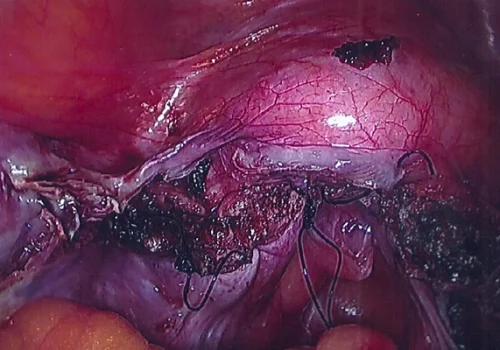

Florid Adenomyosis - Total Laparoscopic Hysterectomy

The pathology specimen revealed florid adenomyosis.